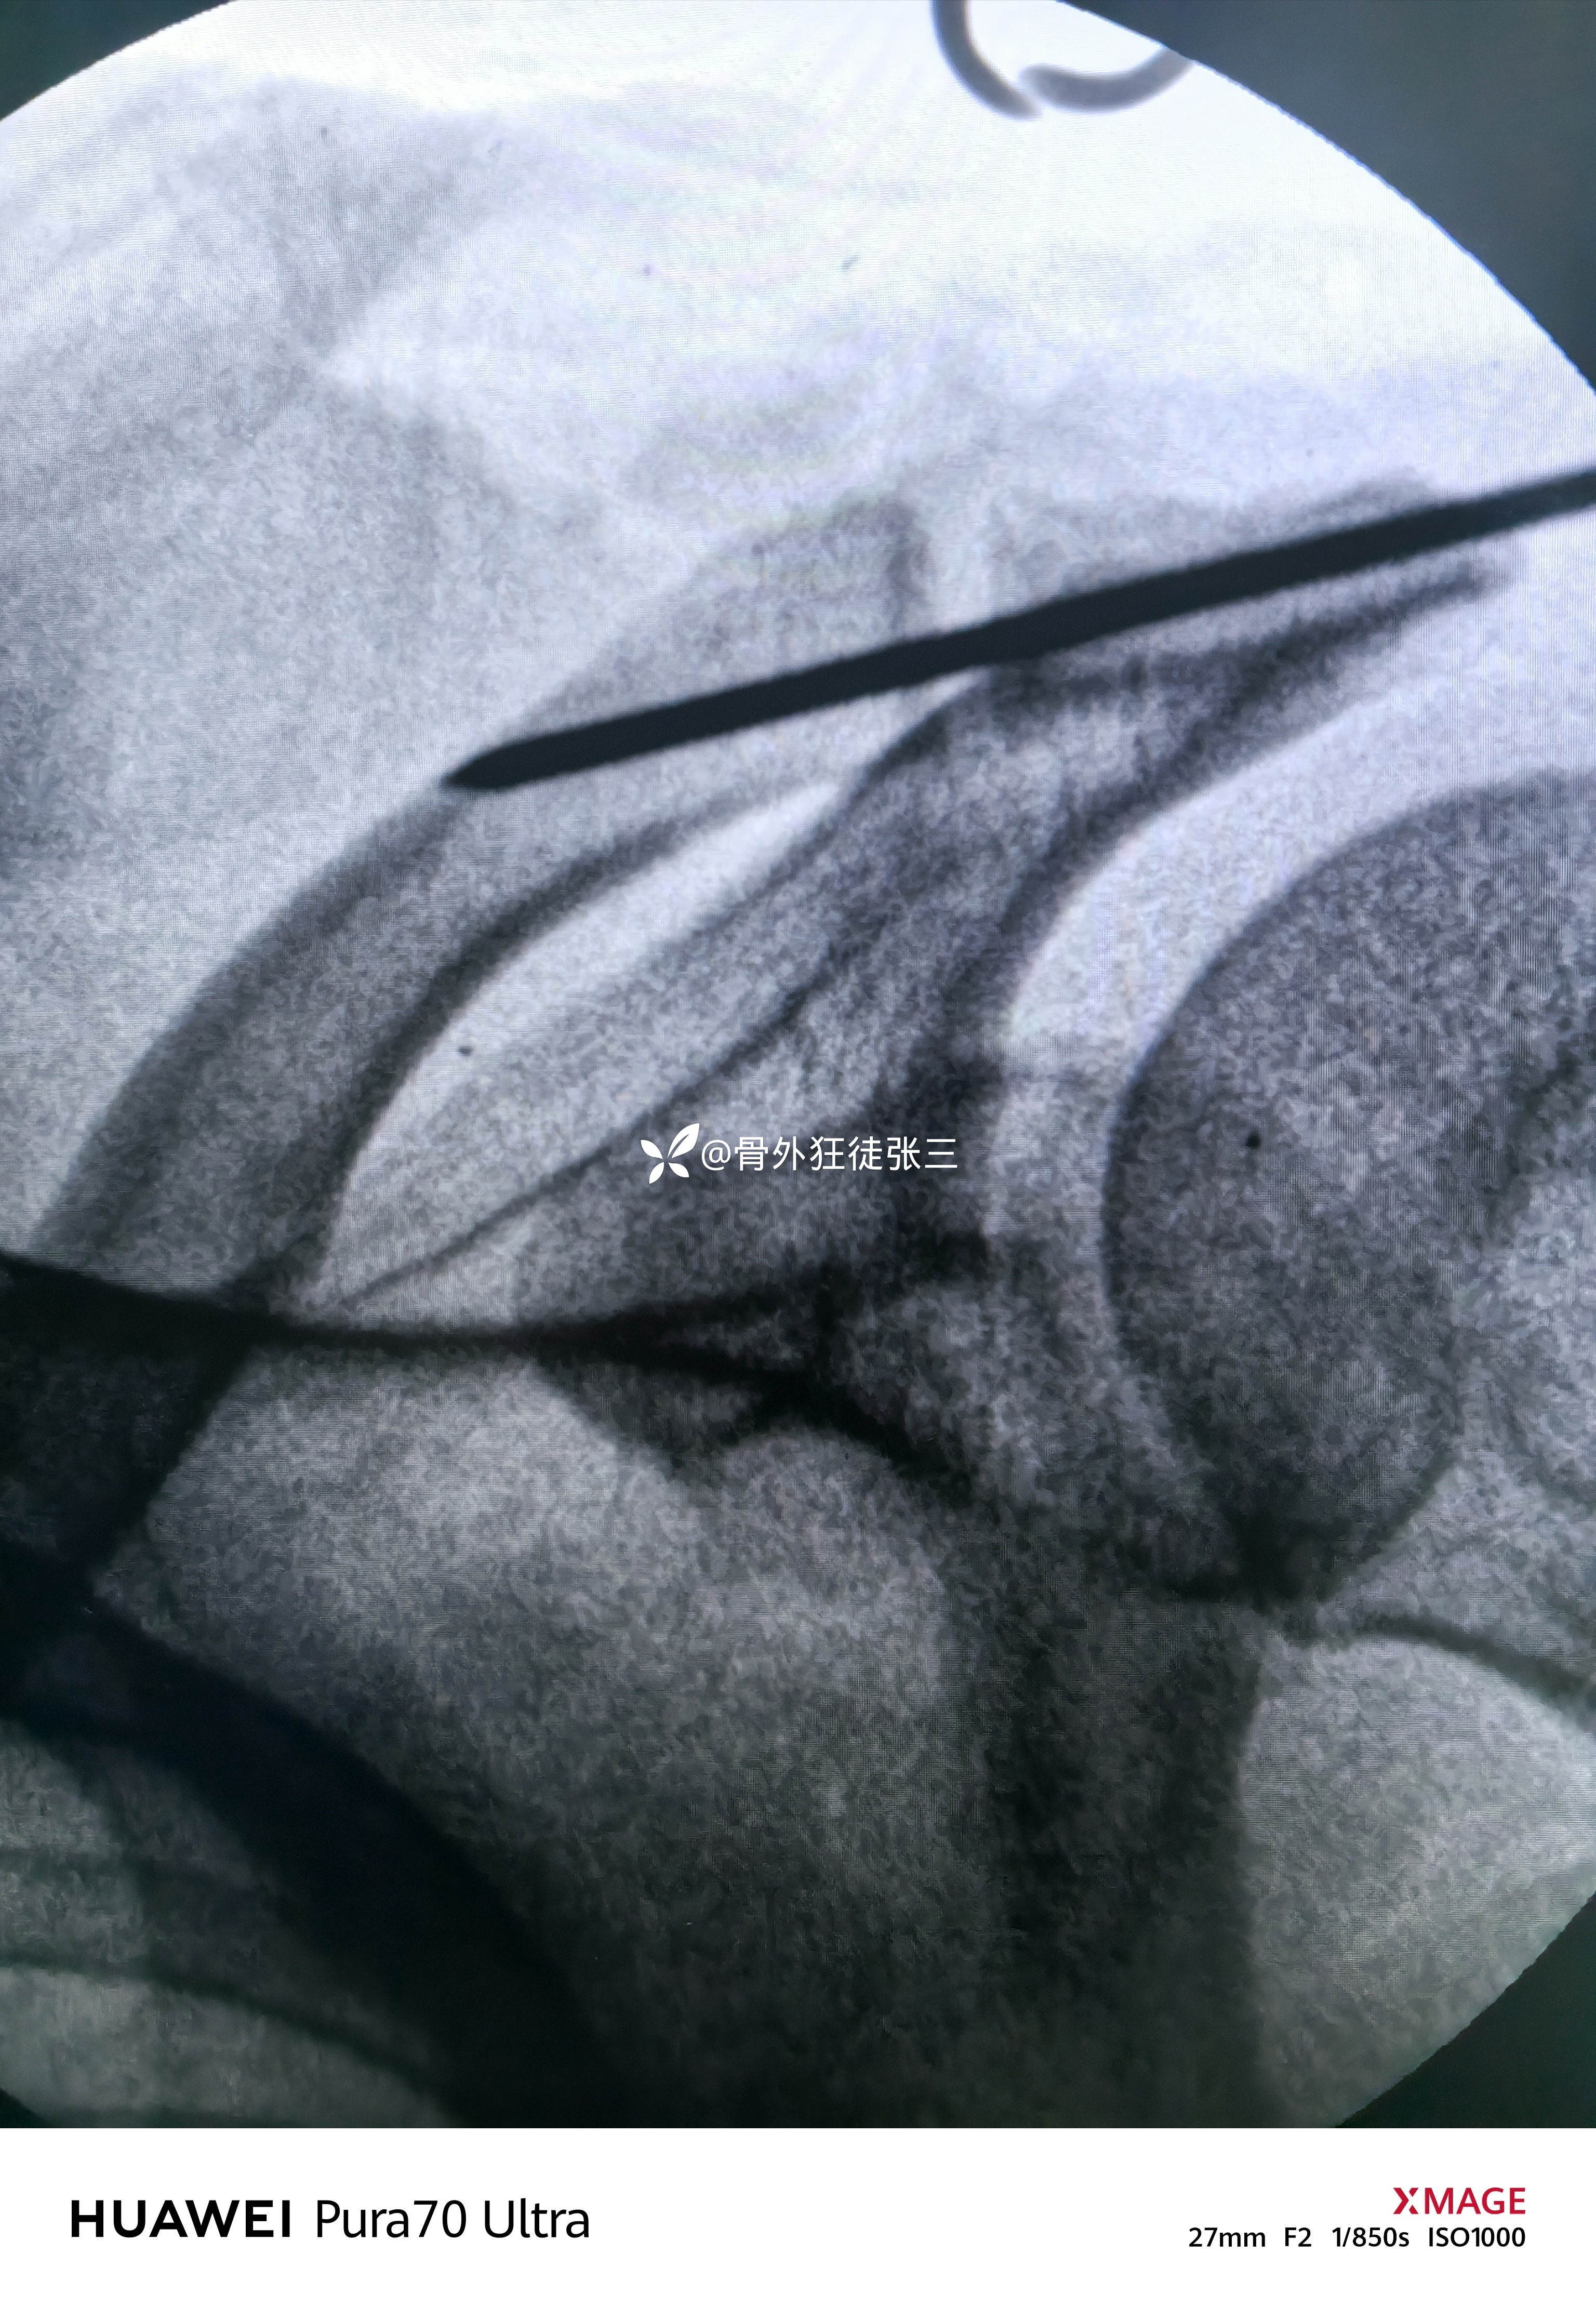

辅助检查:

临床诊断:

右肩锁关节脱位(Tossy分型III型)

治疗经过:

一:以锥状结节为中心做一在锁骨表面的后1/3做一横直行4cm切口。

二,切开锁骨前缘三角肌和胸大肌的附着处。

暴露喙突,用手指向锁骨下探查,可触及血肿和喙锁韧带断端。